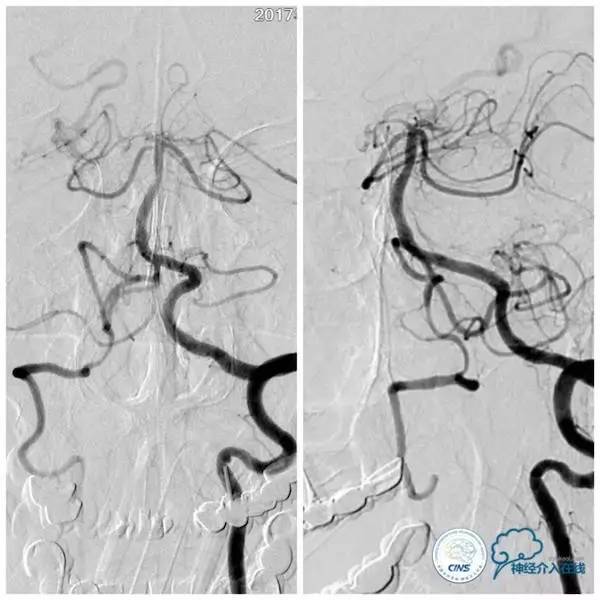

扩张后沿微导丝送入Apollo支架(2.5mm×8mm),释放支架后造影显示支架贴壁良好,狭窄明显改善,前向血流TICI3级(图9,10)。

图9

图10